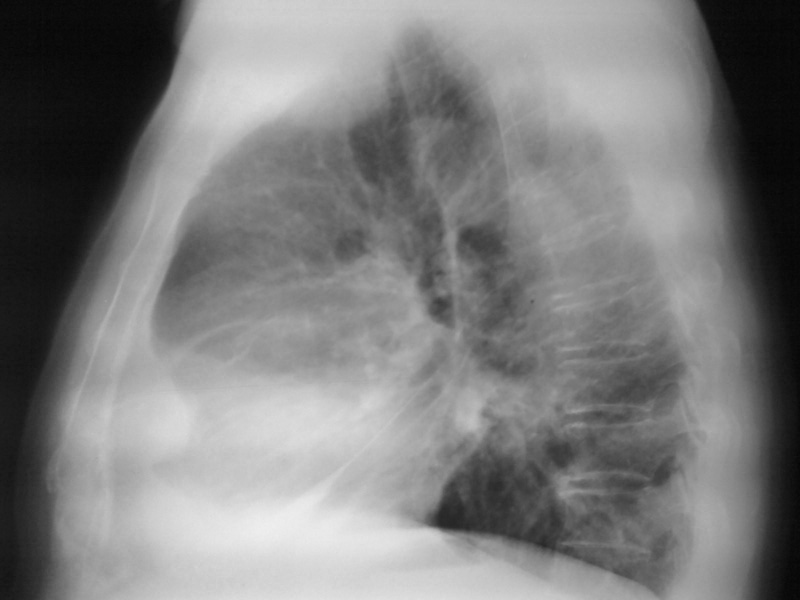

以下是引用李衡钧在2008-6-16 16:46:00的发言:[br]心尖较为陡直,首先考虑冠心病。进一步检查除外室壁瘤。[br]不太像包裹积液和心包囊肿。因为其边缘不是明显锐利清晰。

以下是引用zhangkai在2008-6-16 15:12:00的发言:[br]左下侧胸壁包裹性积液?[br]心脏改变建议结合透视、临床听诊、超声检查排除室壁瘤可能。